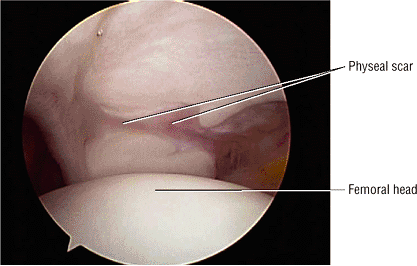

The femoral physeal scar is seen as a horizontal band of low signal intensity in an anterior-to-posterior orientation.

100 asymptomatic patients.53 In another study of renal transplant recipients, followed for 22 months using serial radiographs and MR, untreated AVN was shown to have a benign course without progression from Ficat stage 0.54 Jiang and Shih reported that the presence of a complete or dense physeal scar on MR scans was associated with a high risk for AVN of the femoral head.55 Segmental or incomplete scars in AVN were uncommon. The sealed-off or complete scar was shown to be a risk factor in patients with or without a history of steroid or alcohol abuse (associated lipogenic factors). Because it is possible to identify MR changes of focal osteonecrosis when radionuclide scans are negative and CT and plain film findings are normal,56 a limited or modified MR examination could be used as a low-cost screening tool in at-risk populations.